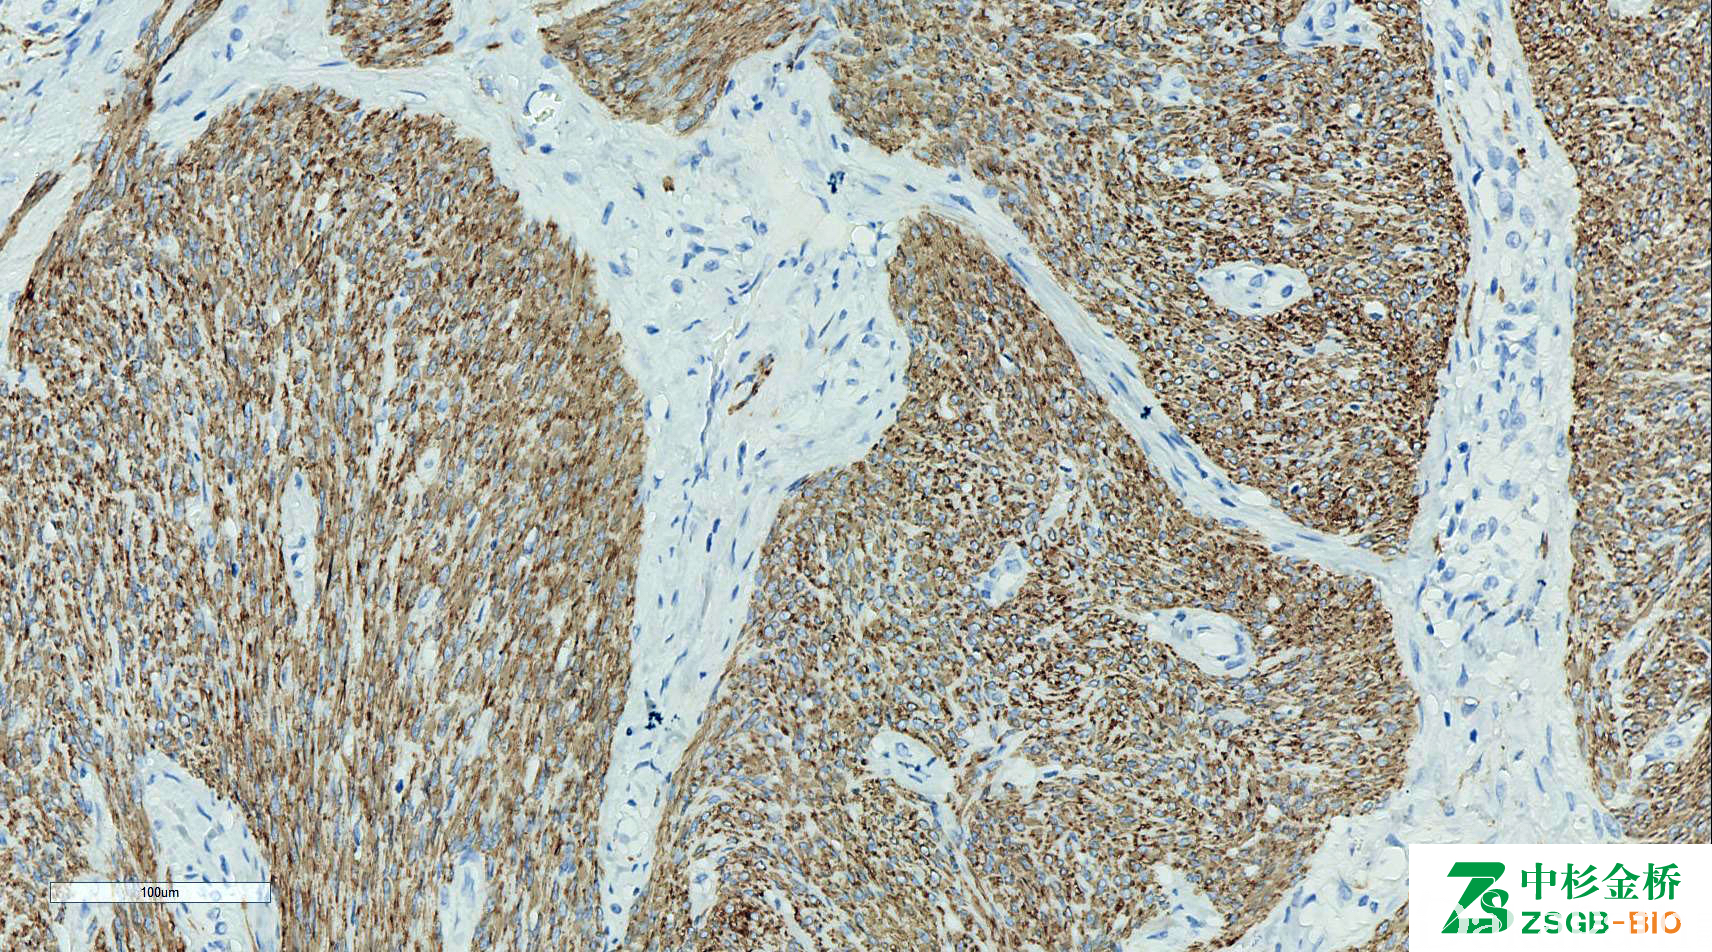

Desmin

中间丝,在肌小节 Z 线附近,存在于平滑肌、骨骼肌和心肌及其肿瘤。

信号定位: 胞质

中杉金桥 | D33 | 1.5 | 3 | 6 | / | 0.1 | 0.2 |